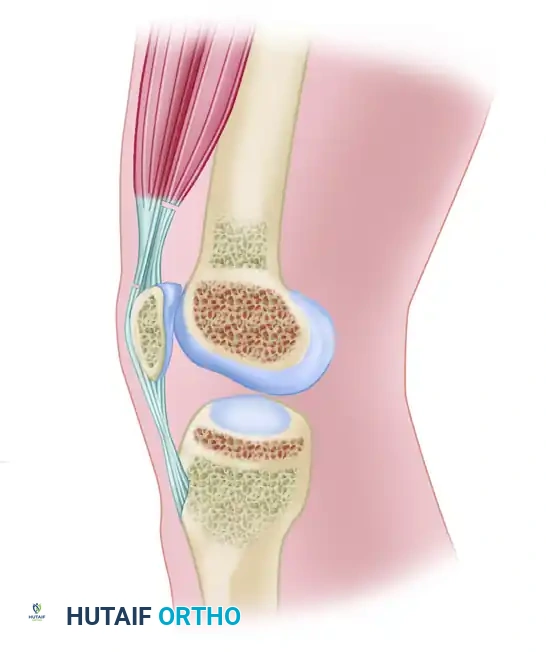

Severe extension contracture of the knee is a profoundly debilitating complication, most frequently arising secondary to distal femoral fractures, prolonged immobilization, or severe soft-tissue trauma. The pathoanatomy is characterized by the obliteration of the normal gliding planes within the extensor mechanism. Specifically, the vastus intermedius undergoes fibrotic degeneration, transforming into a rigid, scarred band that tethers the posterior surface of the rectus femoris and the superior pole of the patella directly to the anterior cortex of the femur.

Pathoanatomy and Biomechanics of Arthrofibrosis

To successfully execute a quadricepsplasty, the surgeon must understand the sequential tethering that restricts knee flexion:

1. Intrinsic Intraarticular Adhesions: Fibrosis within the suprapatellar pouch, medial and lateral gutters, and the anterior interval (the space posterior to the infrapatellar fat pad and anterior to the tibia).

2. Capsular and Retinacular Contracture: Thickening and shortening of the medial and lateral patellar retinacula, as well as the lateral expansions of the vasti.

3. Extrinsic Musculotendinous Tethering: The vastus intermedius adheres to the femoral periosteum, eliminating the excursion of the rectus femoris.